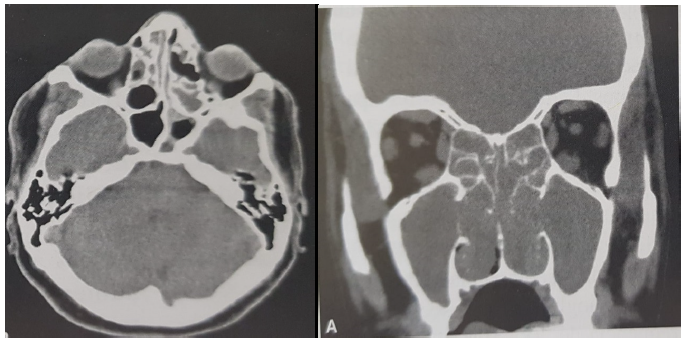

Paciente masculino, 45 anos, relata obstrução nasal bilateral, longa data, com hiposmia. Nega rinorreia importante, dor facial ou outros sintomas otorrinolaringológicos relevantes. Nega, também, tratamento prévio para tal. É tabagista, 20 anos/maço, etilista moderado. História prévia de “bronquite” na infância, com sintomas ocasionais, que relaciona ao uso do cigarro e do álcool.

Após realização de rinoscopia, foi solicitada tomografia da face, que resultou na seguinte imagem:

Considerando as informações, escolha a melhor alternativa.